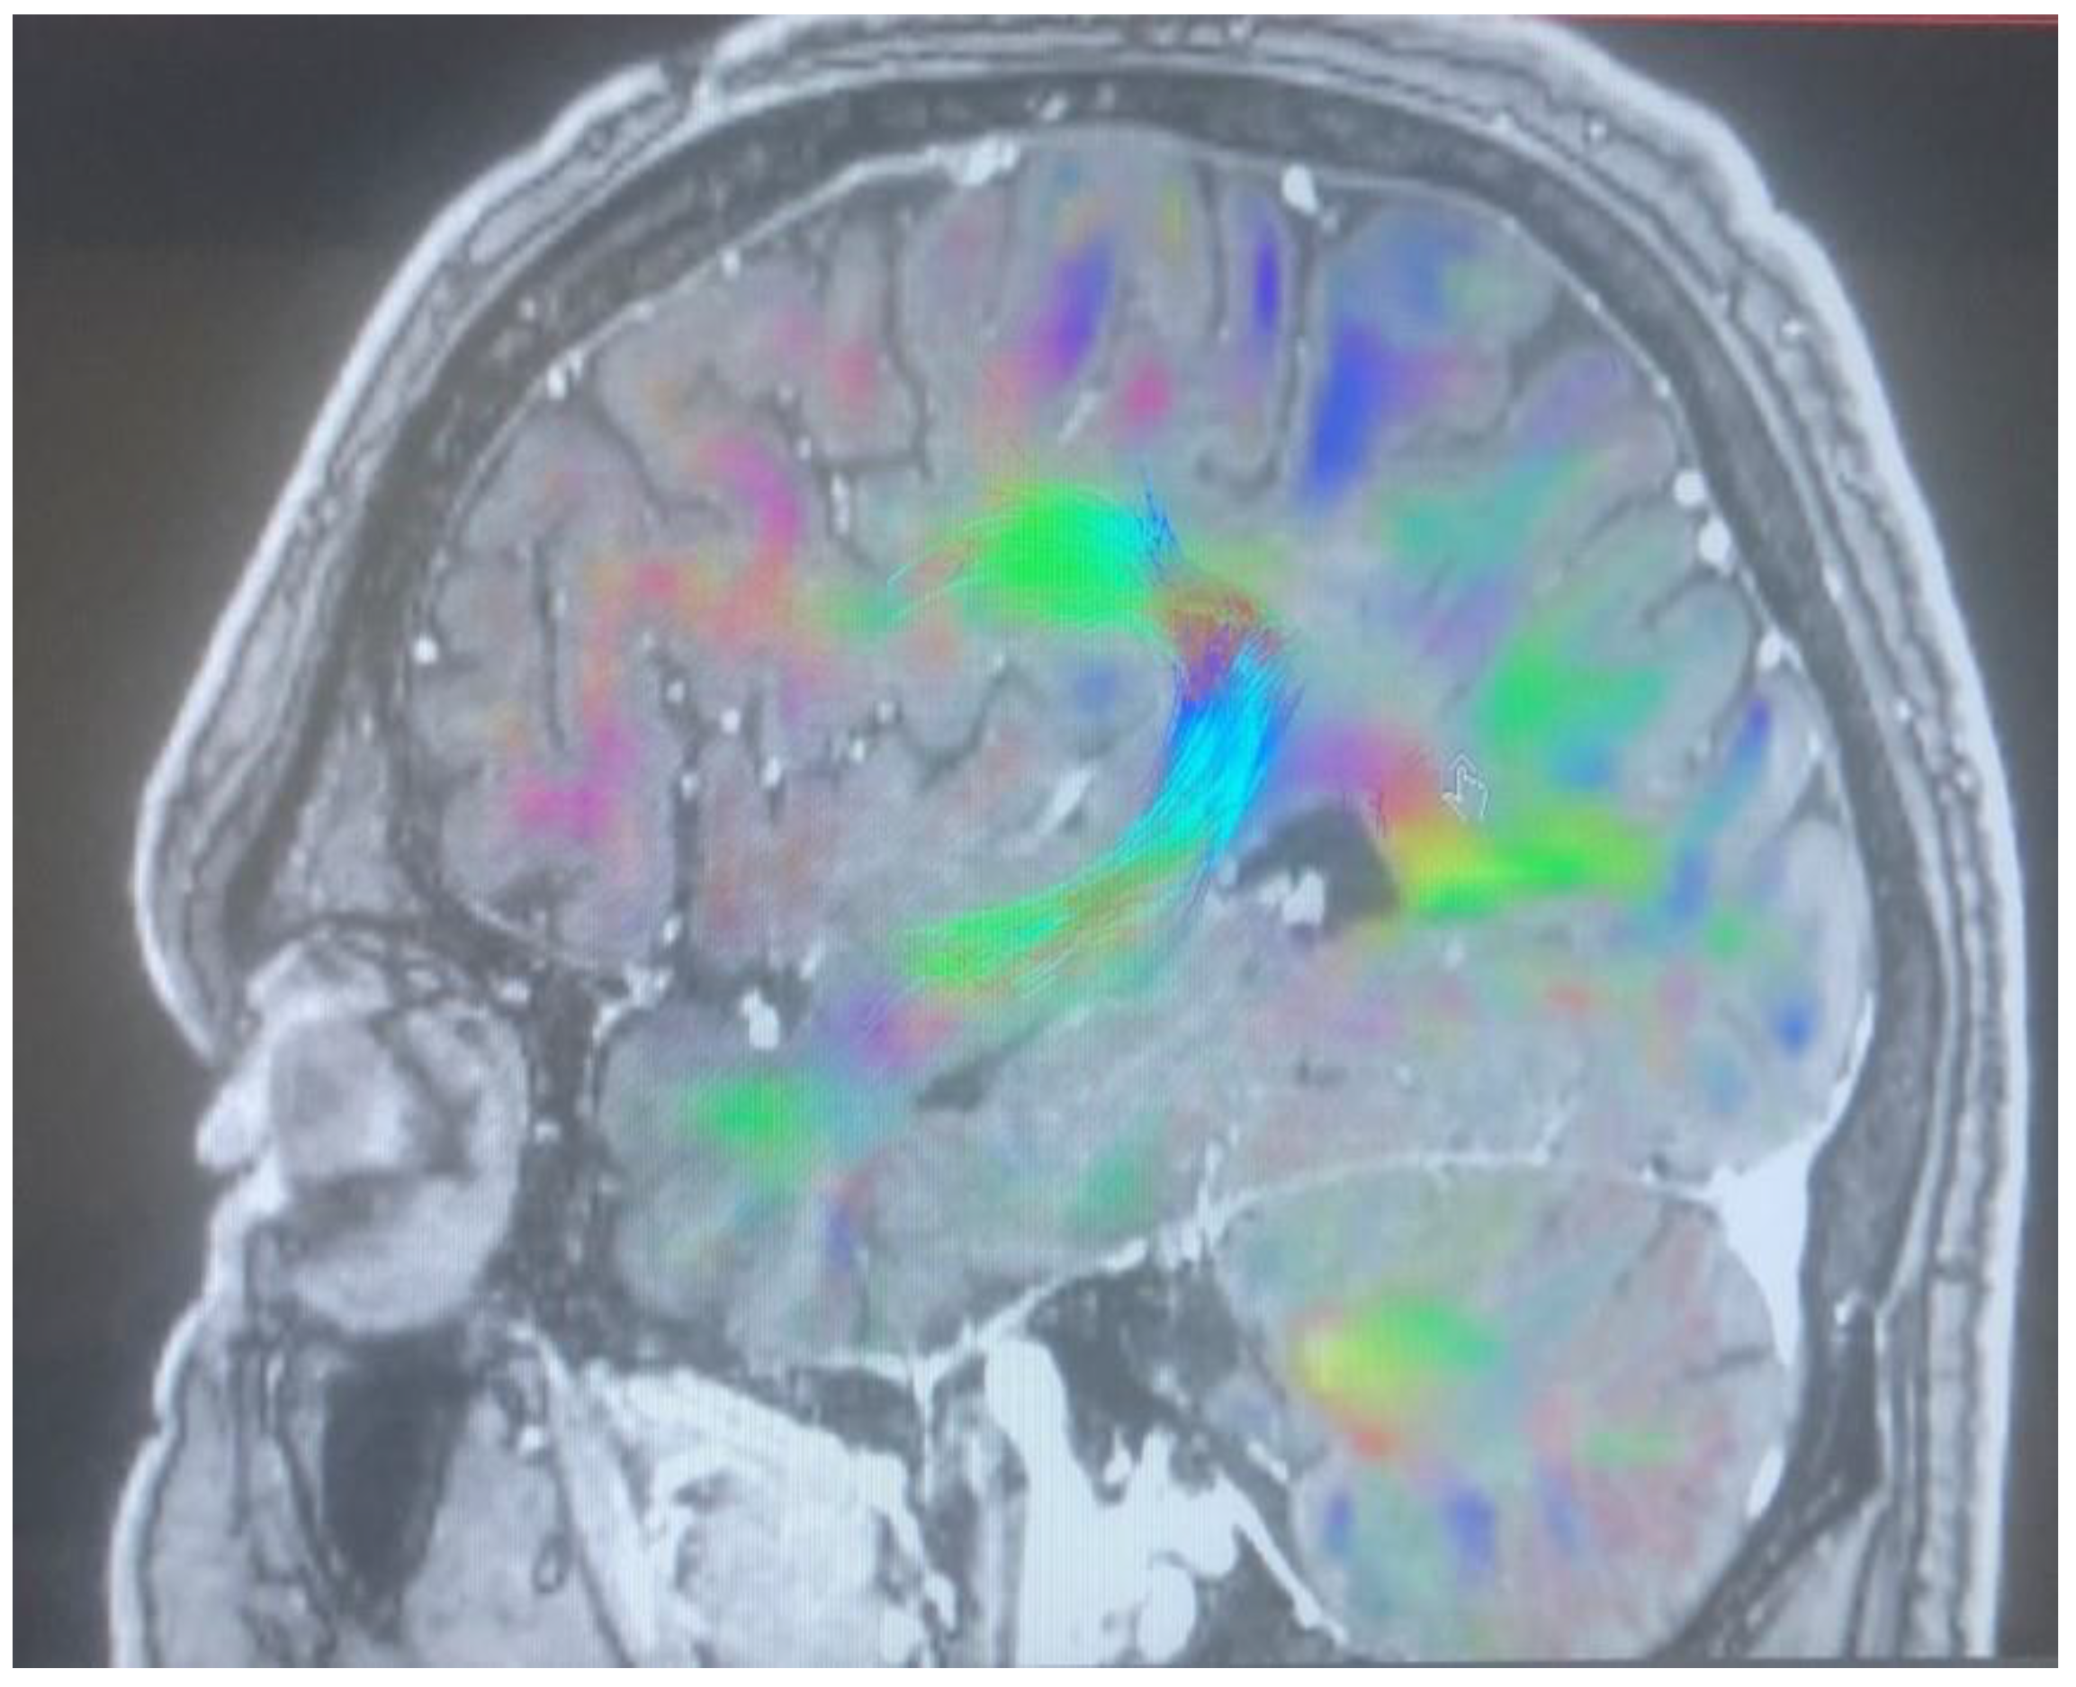

Changes in the anatomy of forceps minor before and after cingulotomy are presented in Figure 2 and Figure 3; moreover, arcuate fasciculus before and after cingulotomy is presented in Figure 4 and Figure 5.

Figure 2. Forceps minor before cingulotomy.

Brainsci 13 00044 g002